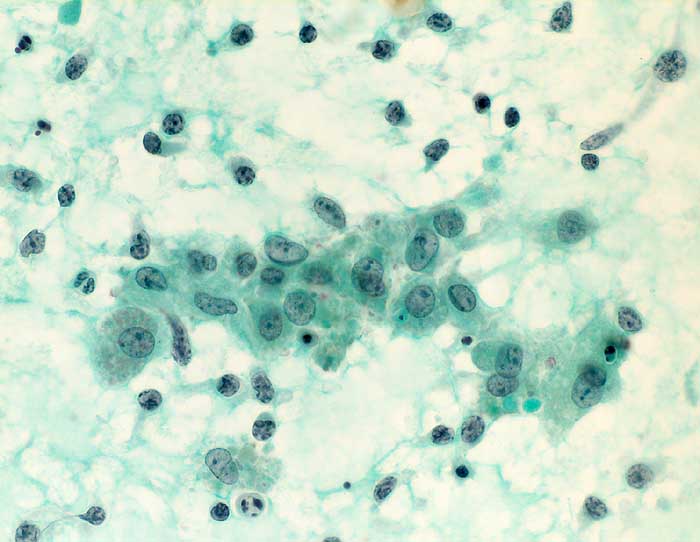

Das Zellbild ist je nach Stadium mehr oder weniger zellreich und zusammengesetzt aus Lymphozyten, Myoepithelien und selten Azinuszellen. Ein lymphozytäres Zellbild ist in Kombination mit dem typischen klinischen Bild (Keratokonjunktivitis sicca, Xerostomie, rheumatische Erkrankung) für die Sicherung der Diagnose ausreichend. Auf die Lippenbiopsie kann in diesem Fall verzichtet werden.